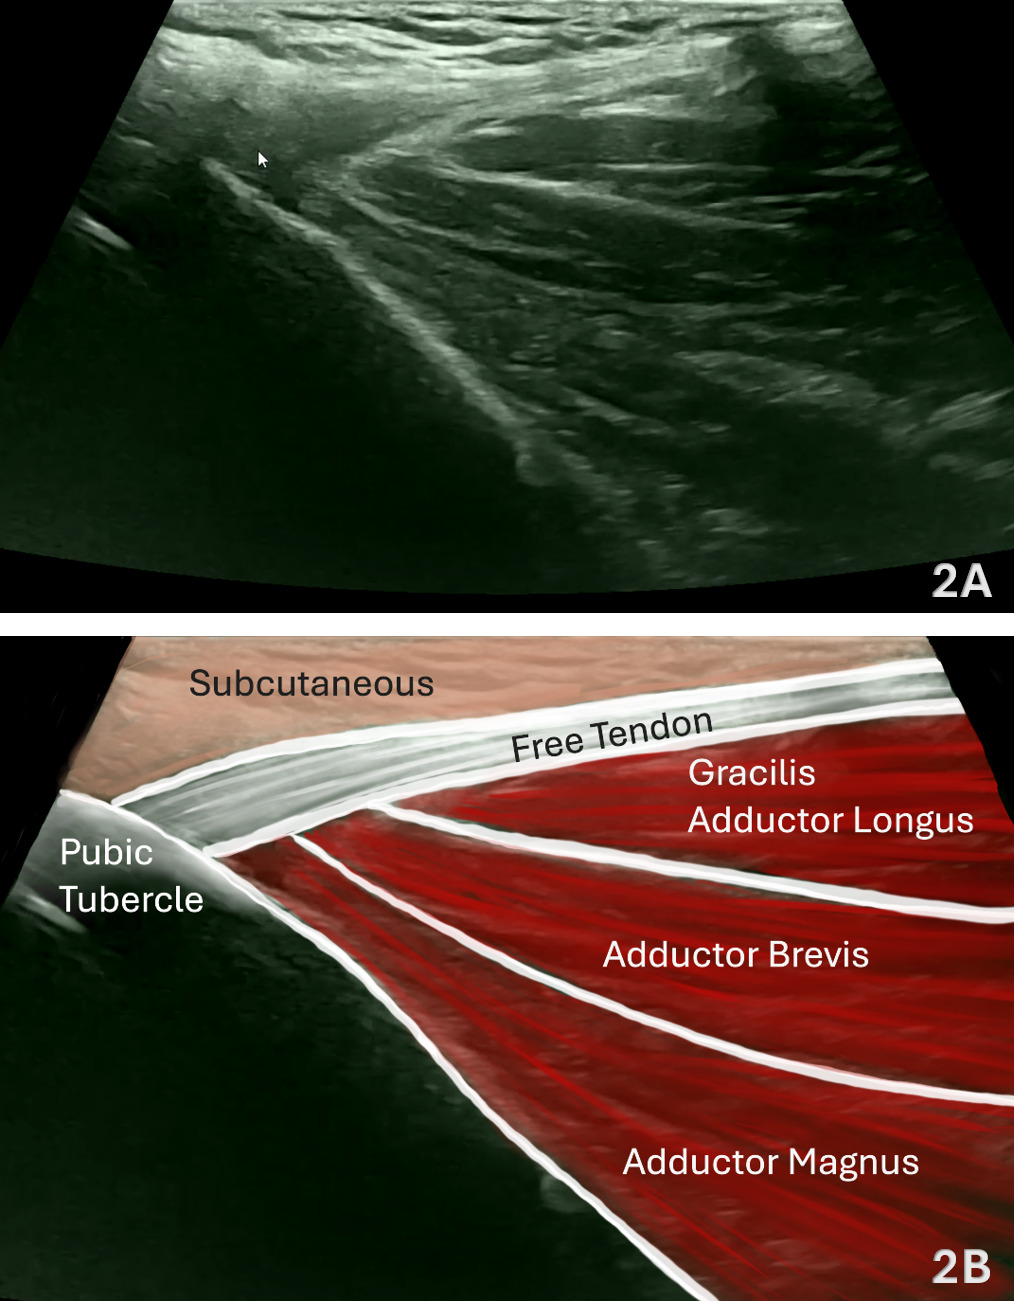

Figures 2A and 2B: Normal Adductor Longus in LAX

Refer to Figure 1B for the transducer position for this image. In LAX, align the transducer parallel to the adductor longus fibers and center the muscle belly longitudinally. The adductor longus appears as a hypoechoic, pennate muscle with a uniformly fibrillar tendon proximally that transitions smoothly into the muscular portion distally. The tendon demonstrates parallel hyperechoic lines converging toward its bony attachment on the pubis, just lateral to the symphysis. Deep to the adductor longus, portions of the adductor brevis and adductor magnus can be visualized, while the gracilis lies more superficial and medial. Optimize imaging so the proximal tendon and its insertion are clearly visualized, positioning the posterior border of the muscle in the lower third of the image with the focal zone at or just deep to this level. Use slight heel-toe adjustments to minimize anisotropy and maintain a consistent insonation angle. Document tendon continuity, echotexture, and thickness at rest, and, when appropriate, during gentle resisted adduction to assess for contractile integrity and pain reproduction.